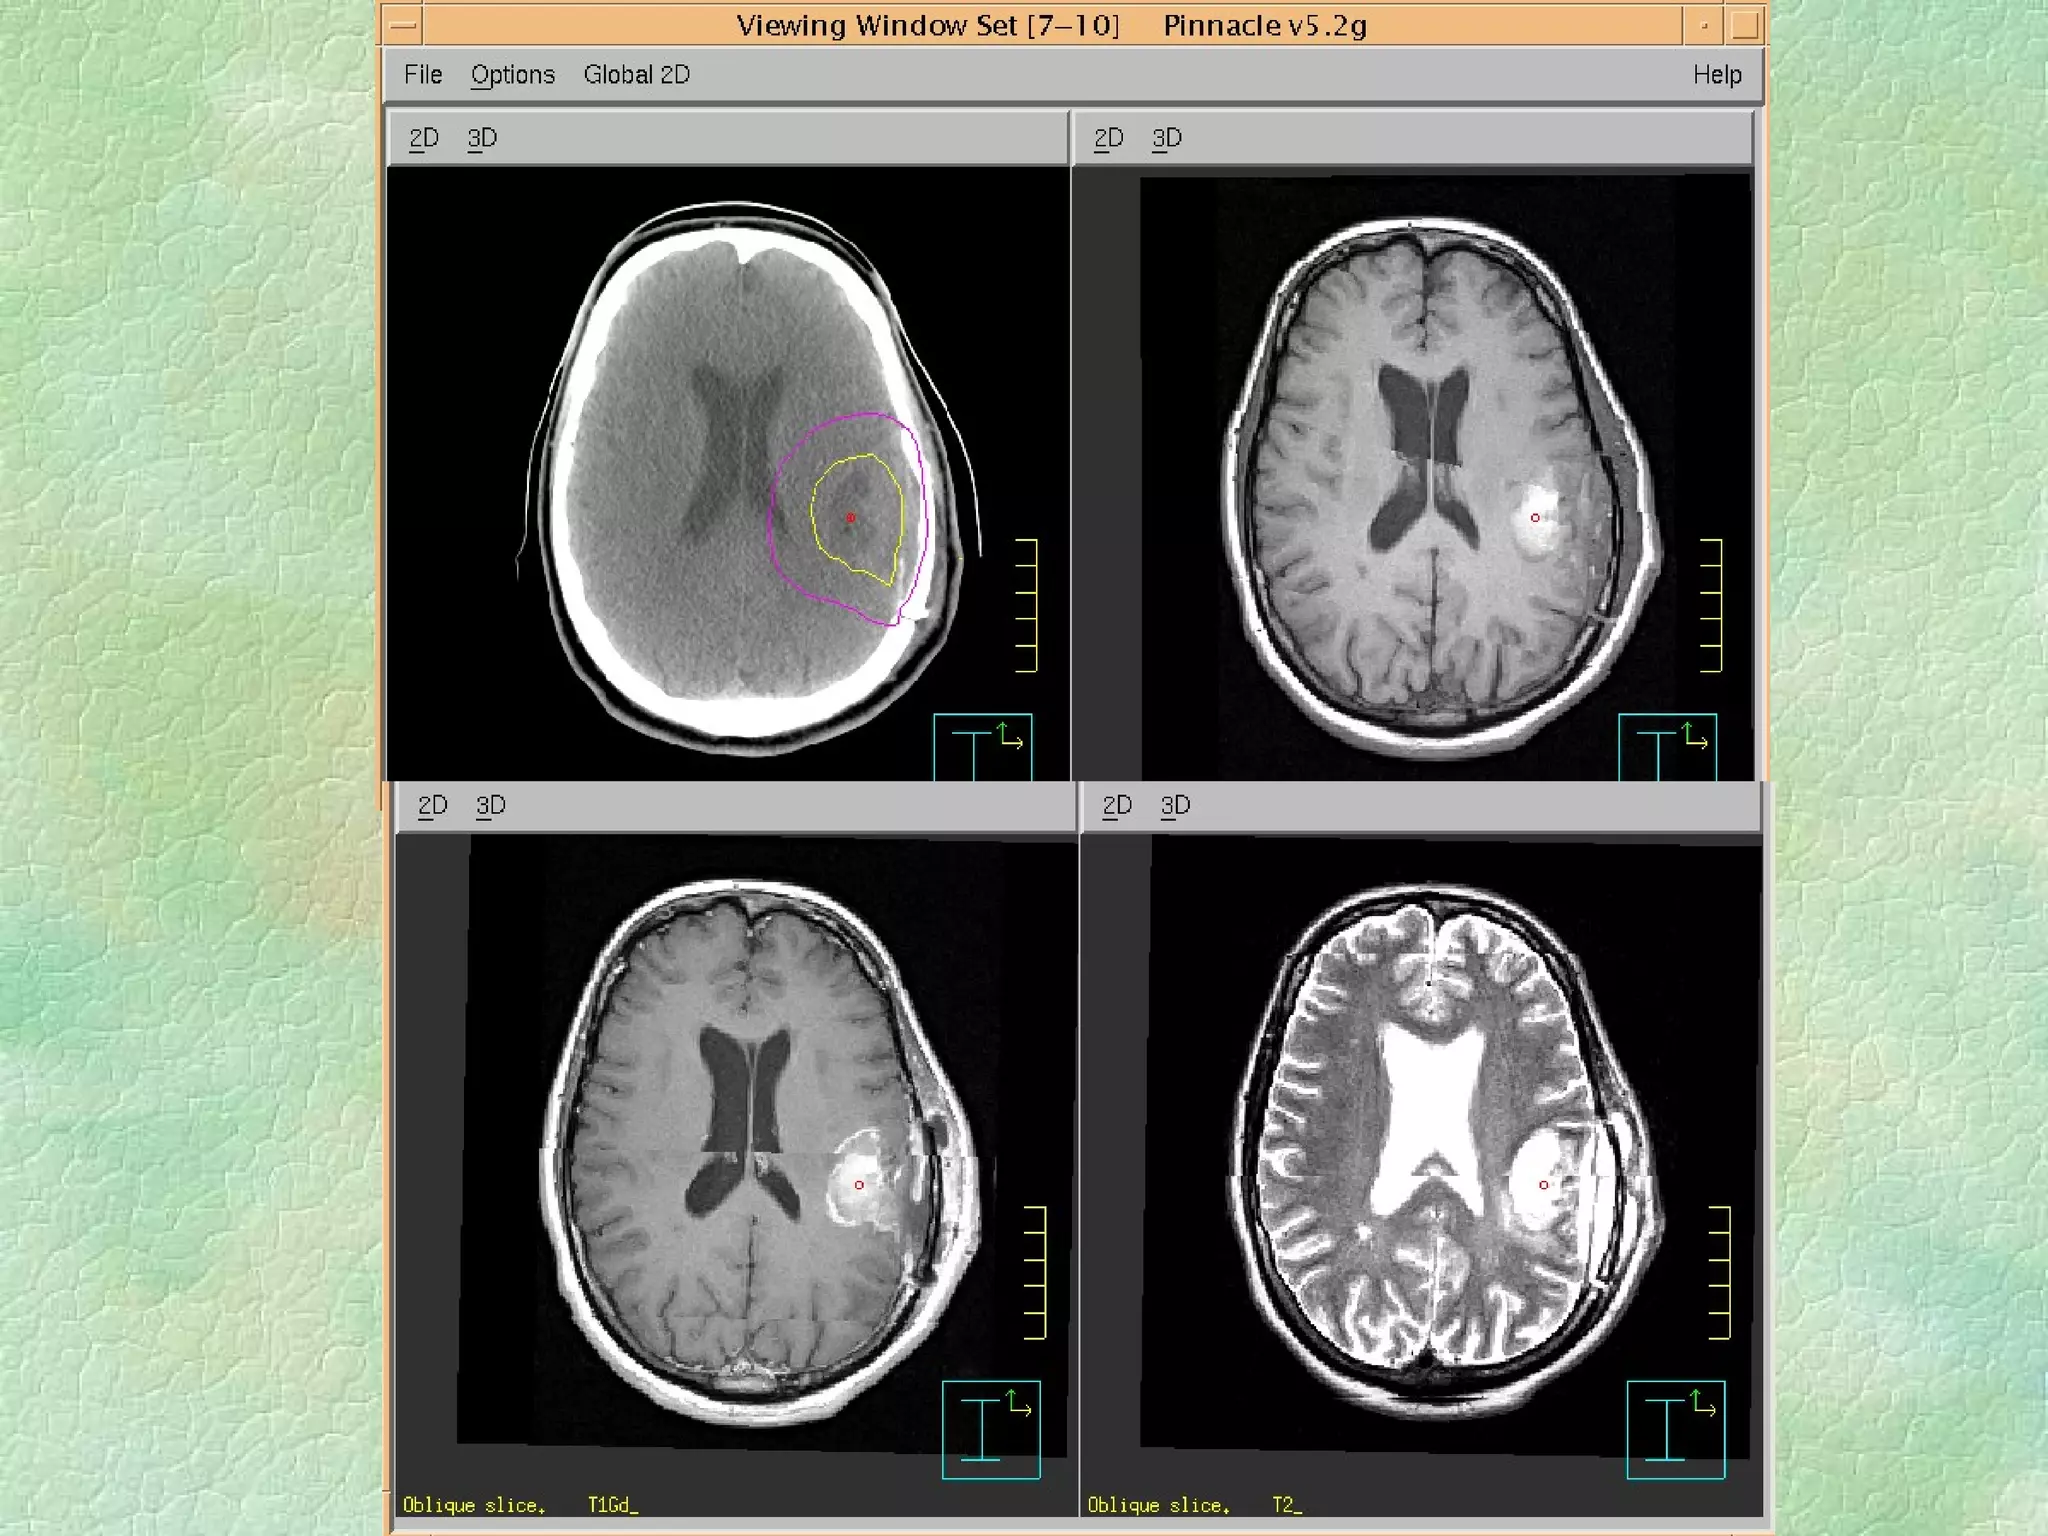

Volume Definition:  Imaging Modalities CT, US, MRI, PET, Nuc Med, Spect fMRI, Optical?, …….. Addition of margins

Virtual Simulation: -  Immobilization CT Coordinate system Structure Delineation Isocentre localization Beam placement/definition

Problems: Images are static and organ motion is not evident Correlation of imager/patient/treatment coordinate systems is non-trivial - DRRs Resolution of data set is limited by slice thickness - structure definition/DRR Imaging modality - image fusion

Problems: Images arestatic and organ motion is not evident Correlation of imager/patient/treatment coordinate systems is non-trivial - DRRs Resolution of data set is limited by slice thickness - structure definition/DRR Imaging modality - image fusion

Advantages: Improved volumedefinition Patient data collected in digital form for dose calculation Speed